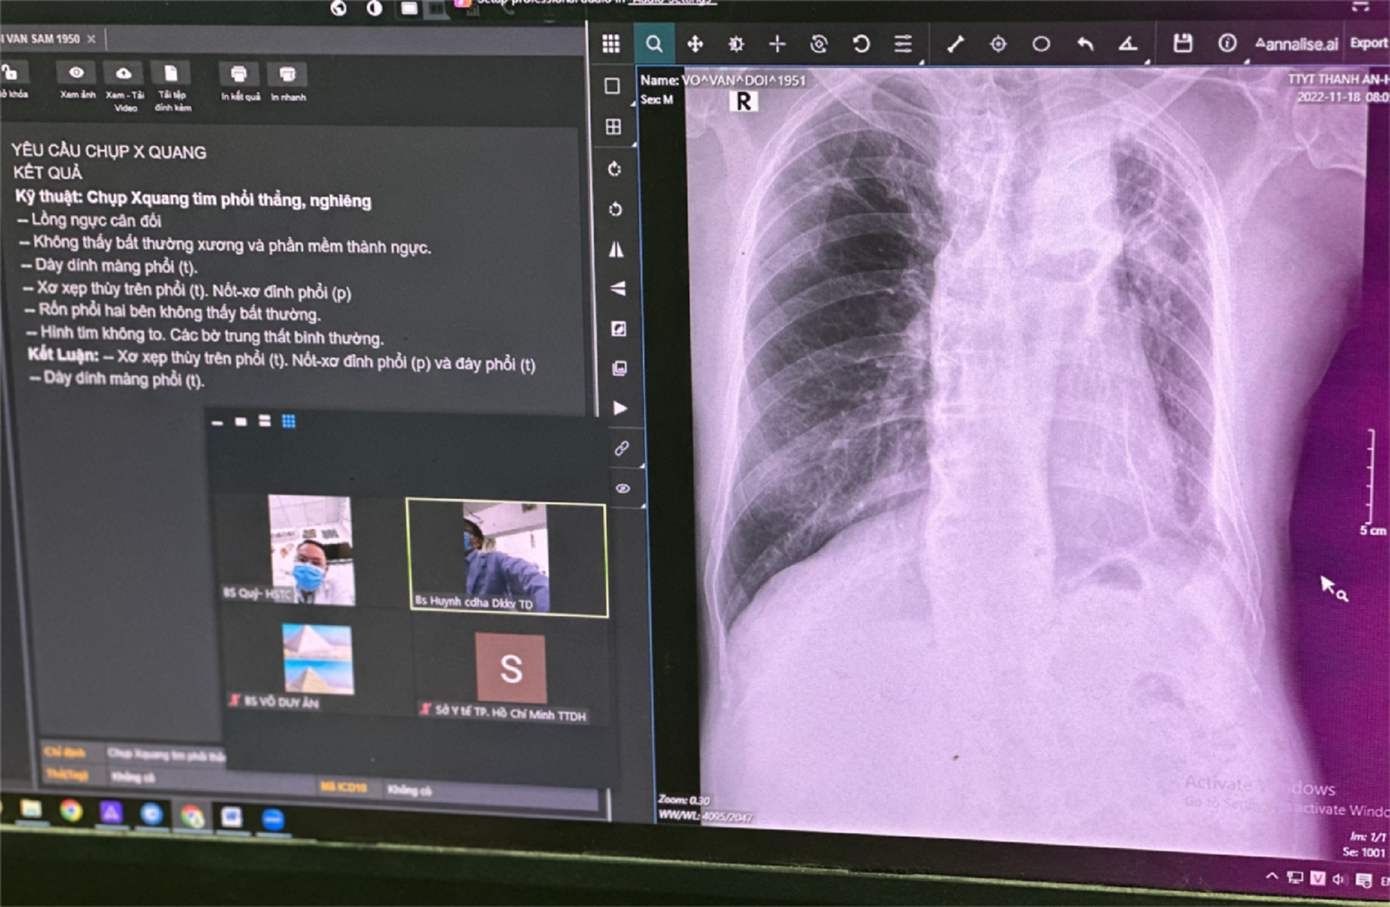

Ngày 18/11, bệnh nhân V.V.D. (71 tuổi) đến Trạm y tế xã Thạnh An để khám và kiểm tra sức khoẻ vì ho ra máu. Sau khi chụp X-quang phổi, các bác sĩ đã ứng dụng AI (trí tuệ nhân tạo) được tích hợp trên máy X-quang kỹ thuật số. Căn cứ trên các thông tin hiển thị trên màn hình, bác sĩ nhanh chóng chẩn đoán bệnh nhân bị xẹp phân thùy phổi bên phải, dày màng phổi và tràn dịch màng phổi bên trái.

Mặt khác nhờ ứng dụng AI máy X-quang đã được kết nối với hệ thống lưu trữ và truyền thông tin hình ảnh y tế (PACS) các bác sĩ tại xã đảo đã dễ dàng kết nối chuyển thông tin, hình ảnh của bệnh nhân và hội chẩn chuyên môn với chuyên khoa của lĩnh vực Hồi sức tại Bệnh viện Đa khoa Khu vực Thủ Đức trong đất liền. Chỉ mất khoảng 15 phút sau hội chẩn, các bác sĩ đã đưa ra phác điều trị tối ưu cho người bệnh.

Đó là hiệu quả của việc ứng dụng trí tuệ nhân tạo và hội chẩn trực tuyến (telemedicine) được Sở Y tế TPHCM chính thức triển khai tại trạm y tế xã đảo Thạnh An thuộc huyện Cần Giờ. Đây là trạm y tế đầu tiên trên cả nước ứng dụng trí tuệ nhân tạo trong chẩn đoán hình ảnh X-quang phổi, thông qua hệ thống PACS và telemedicine để kết nối bác sĩ đang công tác tại trạm y tế với các bác sĩ đầu ngành tại các bệnh viện của TPHCM.

| Thiết bị hiện đại giúp các bác sĩ từ đảo chuyển hình ảnh, thông tin hội chẩn với chuyên gia ở đất liền |

PGS.BS Tăng Chí Thượng, Giám đốc Sở Y tế TPHCM cho biết, ứng dụng AI và PACS trong chẩn đoán X-quang phổi tại những nơi không có bác sĩ chẩn đoán hình ảnh đã được áp dụng nhiều tại các nước phát triển trên thế giới. Việc vận hành quy trình chẩn đoán hình ảnh bằng công nghệ hiện đại bậc nhất tại trạm y tế là lần đầu tiên triển khai trên cả nước. Đây là giải pháp của ngành y tế thành phố nhằm nâng cao năng lực, chất lượng chăm sóc sức khỏe cho người dân trên xã đảo Thạnh An, nơi xa đất liền, điều kiện tiếp cận với dịch vụ y tế từ trước đến nay còn nhiều khó khăn.